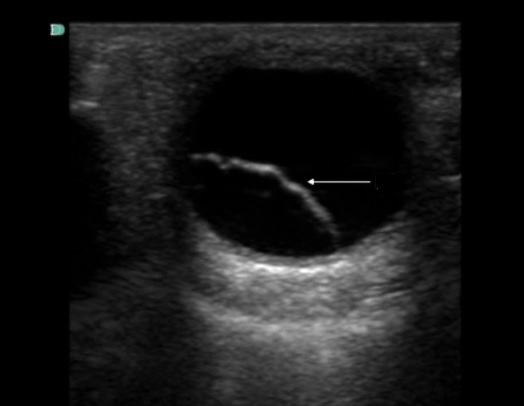

Ocular Retinal Detachment 1 Image

Arrow: Retinal Detachment (RD)